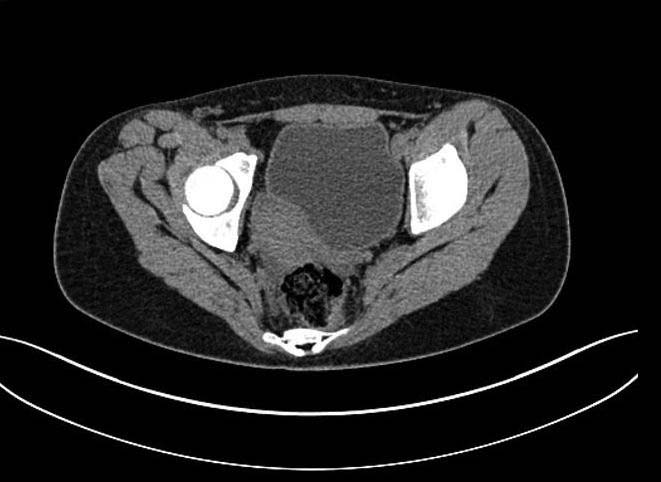

Больная 15 лет. Жалобы: на укорочение правой нижней конечности, хромоту.Анамнез: Со слов болеет с детства, травму отрицает. Ранее за медицинской помощью не обращалась. Последние 2 года отмечает резкое укорочение конечности. Локально: При осмотре отмечается умеренное искривление позвоночника во фронтальной плоскости, умеренная асимметрия лопаток и надплечий. Скошенность таза. Отмечается укорочение правой нижней конечности на 3 см. Движения в тазобедренном и коленном суставах в полном объеме. Нейрососудистых нарушений в периферических отделах нет.

Наверно целесообразно добавить,что болевого синдрома нет,движения в суставе в полном объёме.Я бы уточнил,что жалобы скорее косметического характера(асимметрия при ходьбе и западение вертельной области справа. Укорочение фигурировало как единственный диагноз в направлении на лечение к нам.Компенсация "укорочения" увеличением высоты каблука обуви не устраняет асимметрию таза и в статике и мало улучшает походку.Вопрос-стоит ли в конкретном случае идти на тройную остеотомию таза и латерализацию вертлужной впадины? Мне представляется,что не стоит.